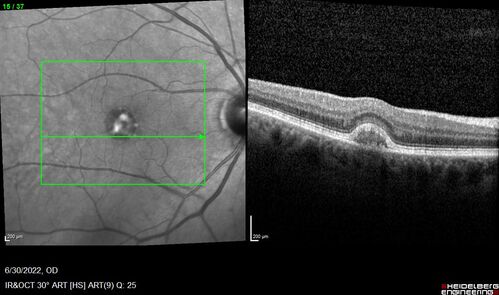

Pattern Dystrophy with Collapsed Vitelliform

74 year old female with vision loss in eye with collapsed vitelliform lesion.